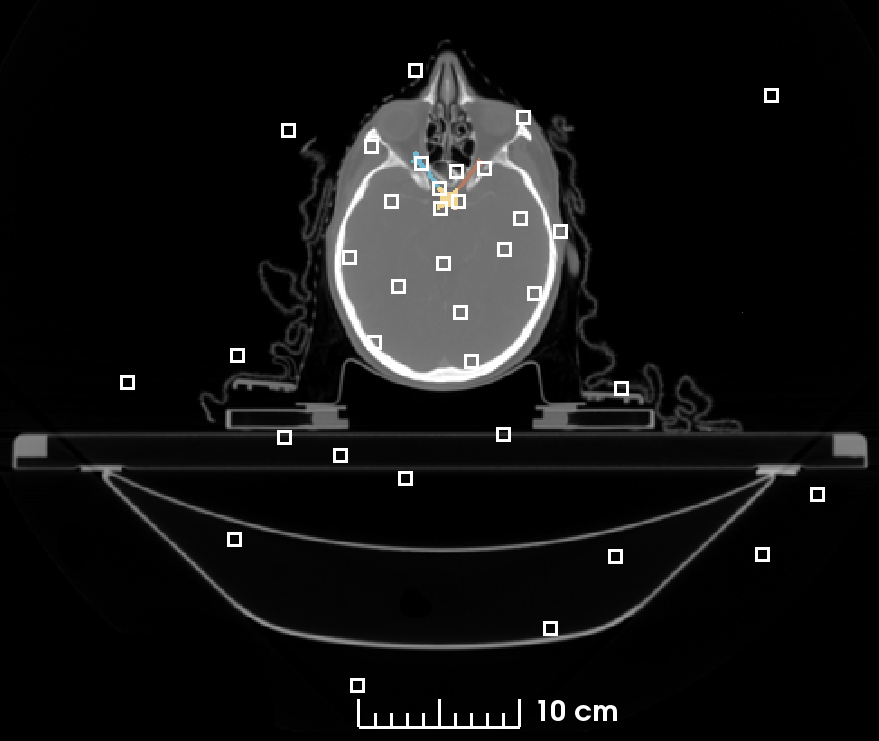

Table 1 shows the average results of the networks trained on the MICCAI 2015 HAN challenge dataset [12], according to the challenge protocol. The results on the test data are evaluated using the DSC, the 95HD as well as the surface Dice (SD) as introduced by Nikolov et al. [2] combining a volume and a surface-based measurement (with surface tolerance τ𝜏\tau identified by the authors in their observer agreement study). The bold values indicate the best results for the given measurement and values marked with stars significance (Wilcoxon signed rank test with p<0.05𝑝0.05p<0.05) over the baseline. Following the work of Li et al. [6] in order to analyze a potential overfitting of the small organs we present in Figure 2 a comparison of the output confidence distribution of the training and the test samples for the segmented organs of our experiments as violin plot. The values in each plot indicate the distance of the average confidence from the training to the test data.

Refer to caption

Figure 2: Violin plot of the output confidence distribution of the training and the test samples for the segmented organs of our experiments, with the distance of the average confidence from the training to the test data indicating the potential of overfitting.

Deviating from the suggestion of the original work of Li et al. [6], Figure 2 does not show the direct network output (the logits) of the segmented classes and its corresponding decision boundaries, which is only possible for up to three classes, but the confidence distribution after the softmax normalization of the eight HAN organs to be segmented. Although no decision boundary can be depicted for more then three classes, the presentation of the organ-wise normalized confidence values allows a direct comparison of the average confidence drift from train to test time and thus the identification of overfitting. The results in Figure 2 confirm the findings of Li et al. [6] for the class imbalanced HAN area and show that the small organs (the Optic Chiasm and the Optic Nerves) are subject to larger differences in training and test time confidence and accordingly prone to overfitting. The measurements also indicate the overall performance enhancement of the ca-Dice loss over the baseline, visible in the increased average confidence values, but do not show a reduction of the overfitting of the small organs by the loss function adaption. Contrary, the experiments with the small patch-size optimized to reduce the class imbalance, show a clear average confidence difference reduction of the Parotid Glands. The Parotid Glands can be considered as mid-sized organs, allowing the assumption that a further reduction of the class imbalance can reduce the confidence drift for the small organs too and hence increase their final segmentation results. The assumption is also supported by the constantly small average confidence drift of the Mandible and the Brainstem being the largest organs with the largest patch ratio and consequently the least overfitting.